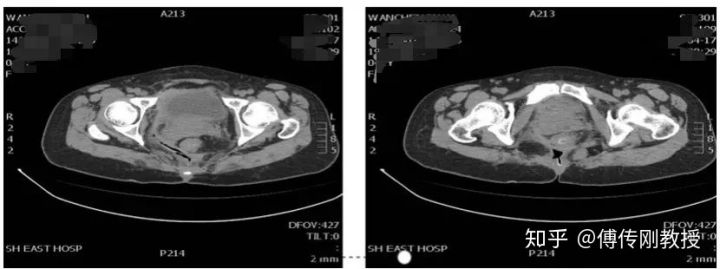

入院腹部CT

2020.01.14医生给我腰麻下行骶尾部窦道切开、脓肿引流术。手术记录显示术中探查齿状线上3cm可触及直肠后壁瘘口约0.5cm,内有少量陈旧性干结大便。囊腔位于直肠右后间隙,约12*10*5cm,内有脓液和少量坏死组织。

腹部CT

好景不长,我出现肛周疼痛,医生给我查体显示骶尾部可见巨大瘢痕,可及一外口,探查长约15cm左右,无渗血,直肠指诊齿状线上5cm触及粪块,指套无染血。医生诊断为:盆腔畸胎瘤(经骶切除术后),乙状结肠造口术后,盆腔巨大囊肿。